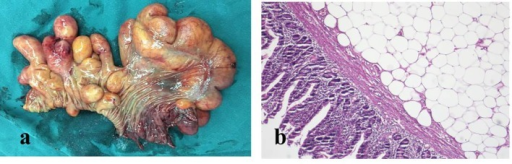

A lipoma is a benign tumor composed of adipose tissue that typically develops just beneath the skin.

Lipomas are most commonly seen in adults.

Lipomas may be treated by surgical excision.

Definitive diagnosis of lipoma is made by pathology showing a well circumscribed mass composed of benign adipocytes.